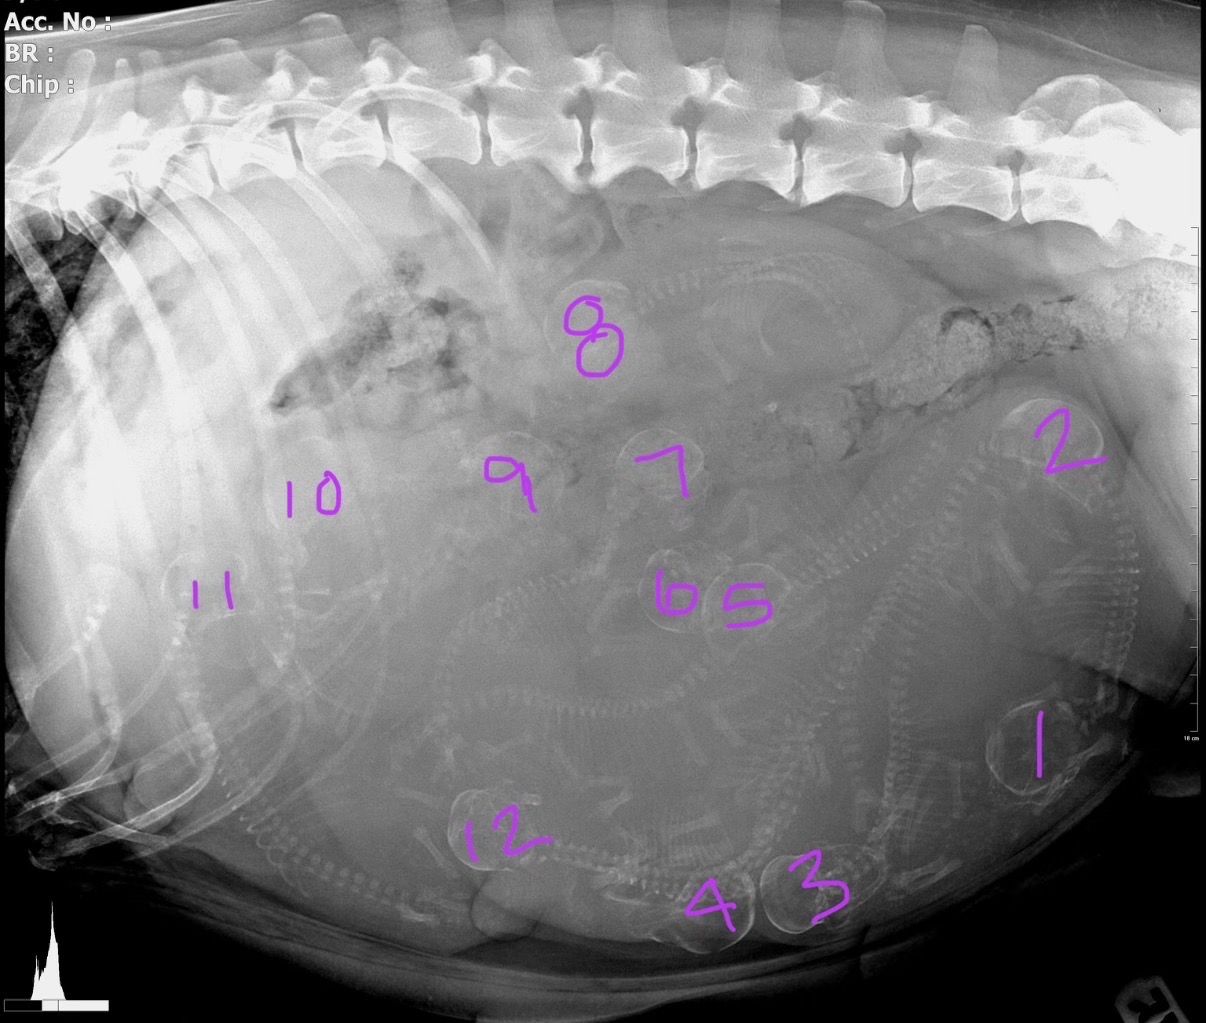

Scotty is RELIABLE. His most recent litter, born 3/12/26, brought TWELVE beautiful healthy puppies! Swipe to see pics! We’re so excited to see their coats darken over time.